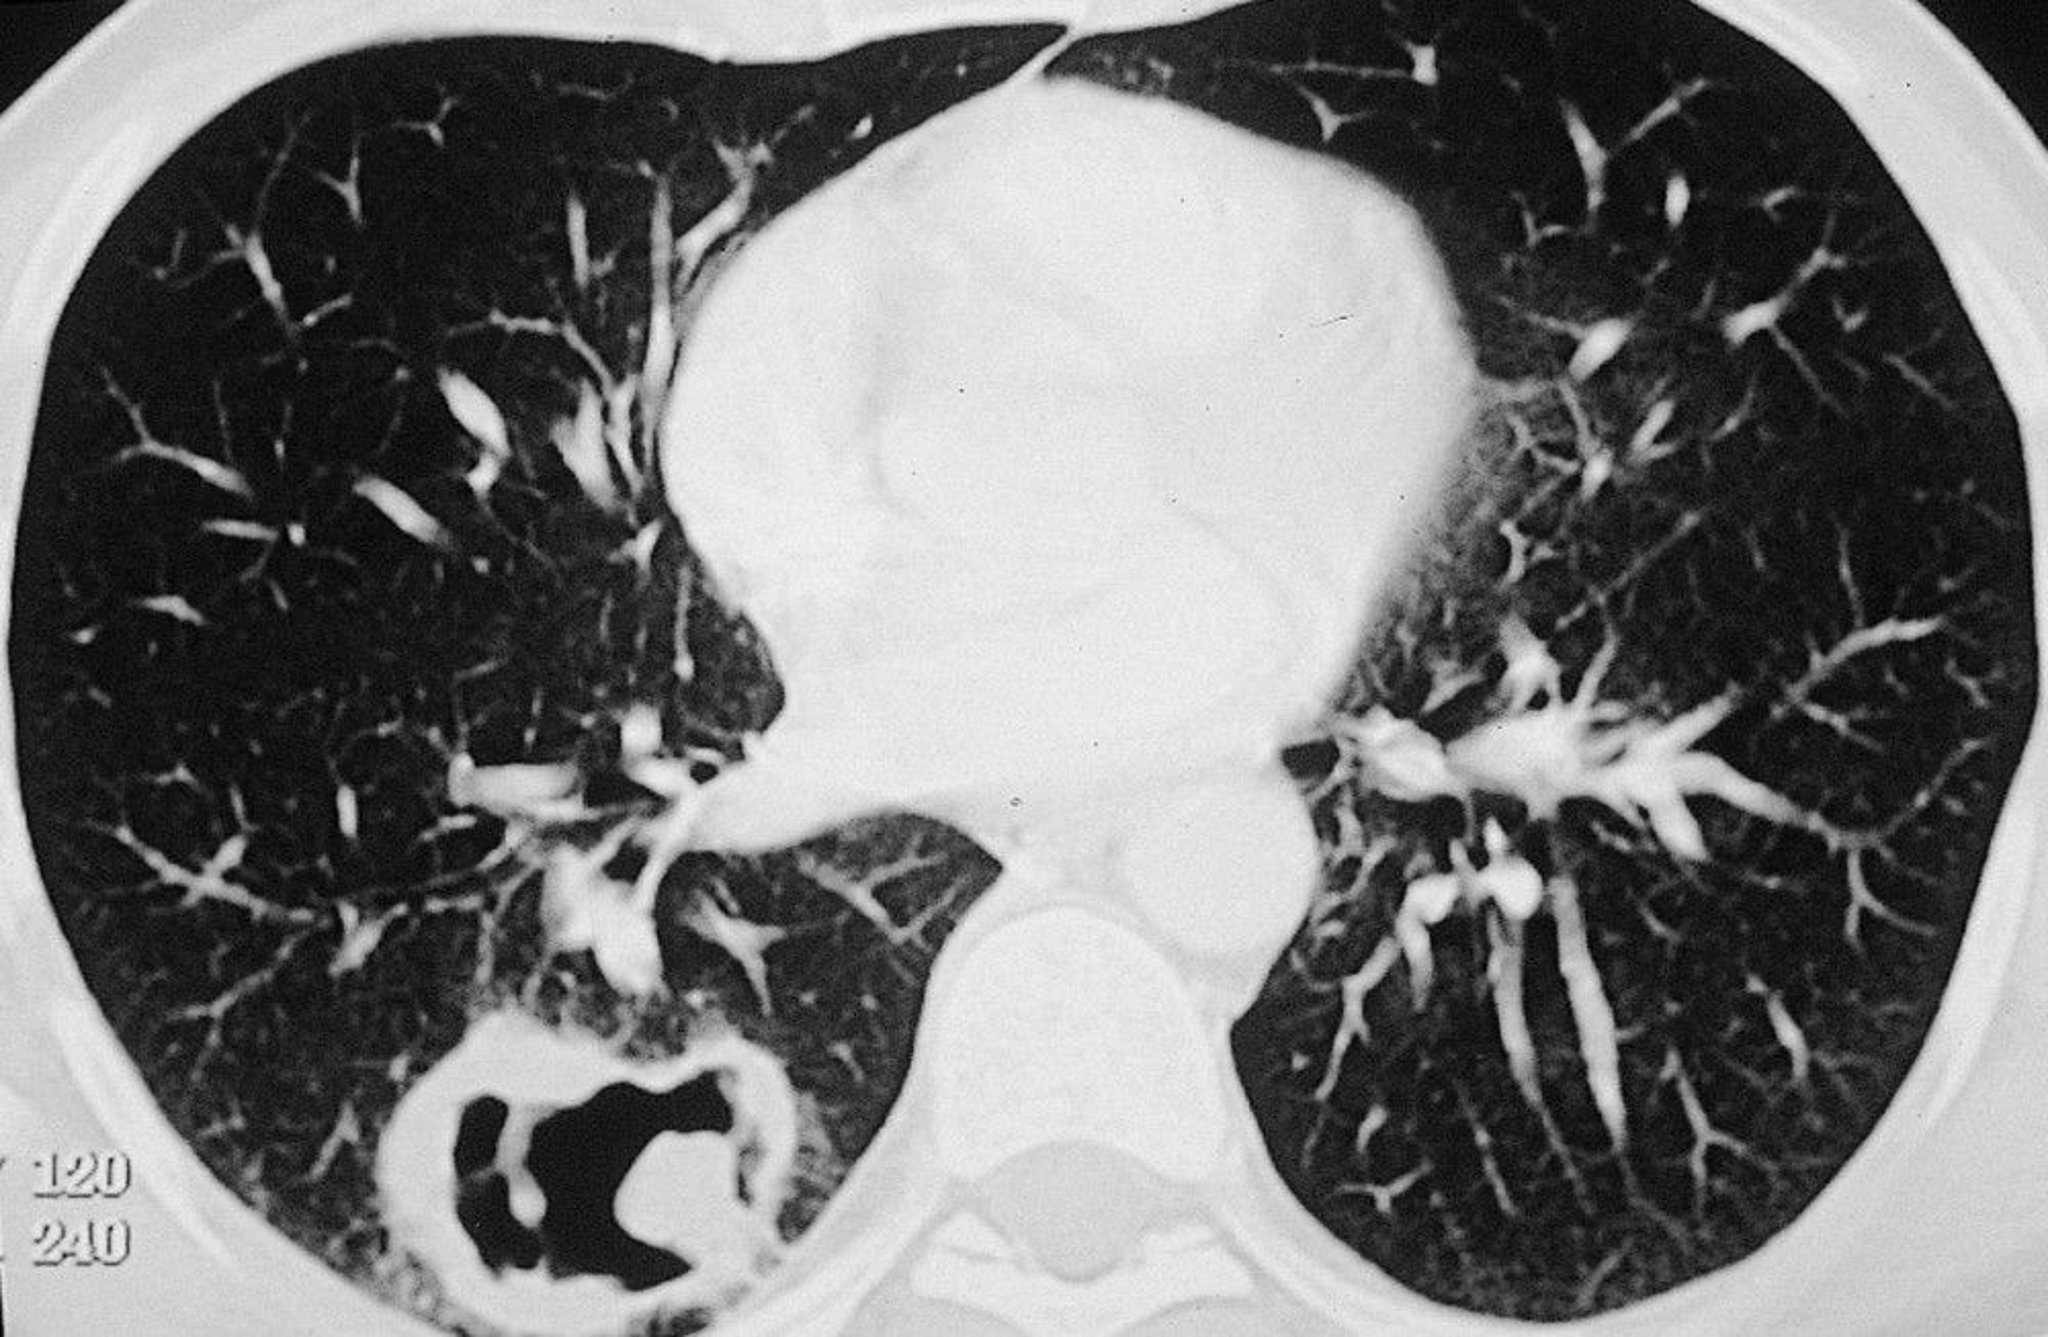

Granulomatosis with Polyangiitis (Pulmonary Lesion)

Large cavitary lesion in right lung in a patient with granulomatosis with polyangiitis (GPA).